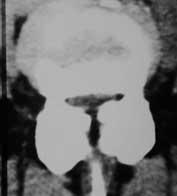

Das CT ist als Röntgenuntersuchung besonders geeignet für die Darstellung von Knochen. Weniger gut werden Bandscheiben und Nerven sichtbar.

Umgangssprachlich wird sie auch als die "kleine Röhre" bezeichnet, da die Gerätetiefe nur etwa 40 cm beträgt. Platzangst brauchen Sie hier nicht zu befürchten!

Nachteil ist die nicht unerhebliche Strahlenbelastung.

Der Patient liegt auf einem verschieb- baren Untersuchungstisch.

Röntgenröhre und Detektor werden kreisförmig um die zu untersuchende Körperregion gedreht.

Nur bei besonderen Fragestellungen ist es sinnvoll Kontrastmittel für eine CT-Untersuchung zu geben.

Ohne Übertreibung kann gesagt werden, daß die neurochirurgische Diagnostik mit Einführung der CT in den 70er Jahren eine neue Dimension erhalten hatte.

In der heutigen Generation stehen hochentwickelte CT- Geräte zur Verfügung.